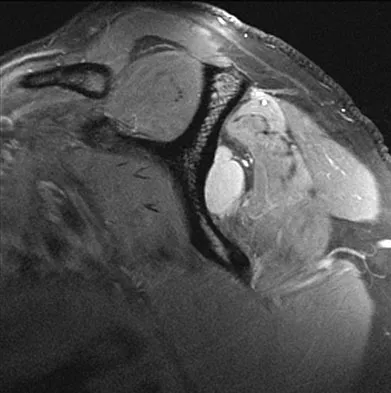

Figures 39a and 39b show the MRI scans of a 25-year-old man with right shoulder pain. Figure 39c shows the arthroscopic view from a posterior portal in the beach chair position. What is the most likely diagnosis?

Explanation